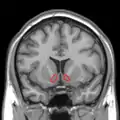

MRI coronal slice showing nucleus accumbens outlined in red

Sagittal MRI slice with highlighting (red) indicating the nucleus accumbens.